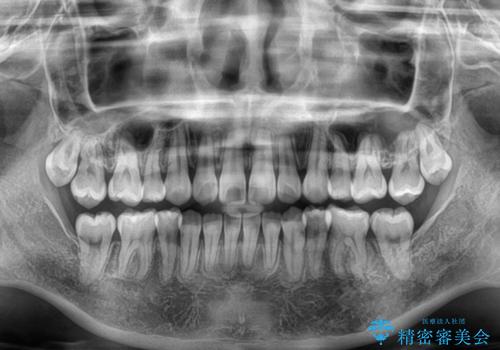

デコボコだらけの歯列をきれいに ワイヤー装置での抜歯矯正治療

- 上下前歯のデコボコを気にして来院された患者様です。

口元の突出感はあまりなかったものの、デコボコを非抜歯で改善すると出っ歯になる可能性があるため、上下左右の第一小臼歯4本を抜歯し、ワイヤー装置にて矯正治療を行うこととしました。

口元の突出感はなかったものの、捻転や八重歯を改善するために補助装置を併用する必要がありました。

予定の2年半を越えてしまいましたが、無事にきれいな口元に仕上げることができました。